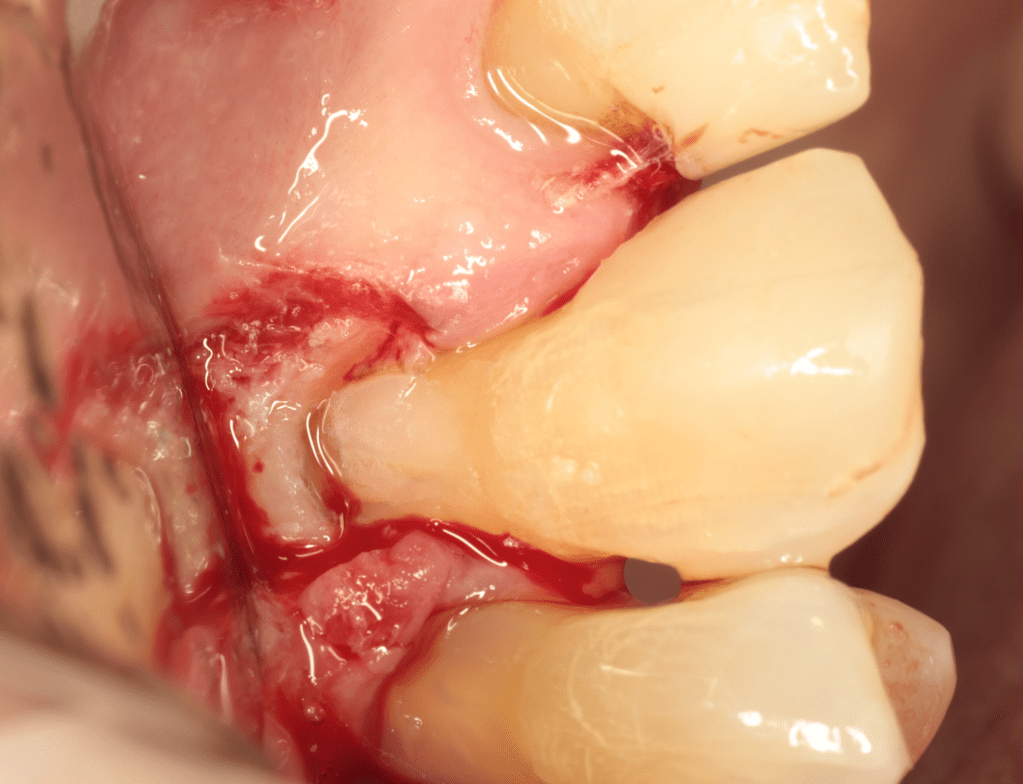

Reabsorción externa, tratamiento quirúrgico

REIMPLANTES

Intencional por dificil acceso coronal y quirúrgico

Reinplante por fracaso de tratamiento

Reimplante, istmo apical, curación cortical palatina 1 año